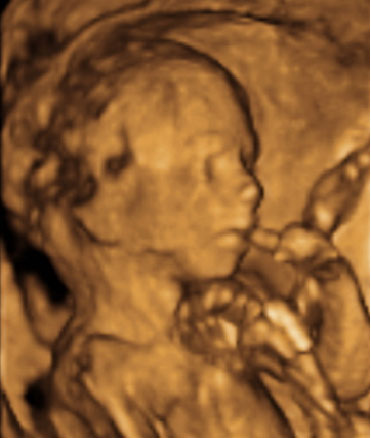

Ecografía: Cara de un bebé de 18 semanas de gestación

Hay movimientos del bebé al nacer que ya ha practicado dentro del útero materno. Esta ecografía en 4D ha captado a este feto de 18 semanas de embarazo cubriéndose con sus manos su cara, en un movimiento muy característico de los recién nacidos.

Ecografía de un bebé de 18 semanas de gestación

Aparece con los brazos por delante, en un gesto de protección que es típico de los recién nacidos, y que seguramente seguirá haciéndolo durante su primera infancia.